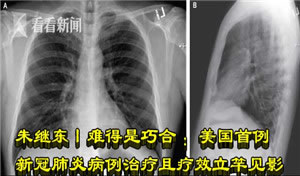

朱继东丨难得是巧合:美国首例新冠肺炎病例治疗且疗效立竿见影

难得是巧合:美国吉利公司德抗病毒新药remdesivir用于美国首例新冠肺炎病例治疗且疗效立竿见影美国前国防部长拉姆斯菲尔德曾是吉利德公司董事会主席和大股东率先在国内报道鼓吹吉利德特效药的药明康德正是因要把5000多中国人血清谎报为犬血清偷送出境外而被处罚的那家外资背景公司